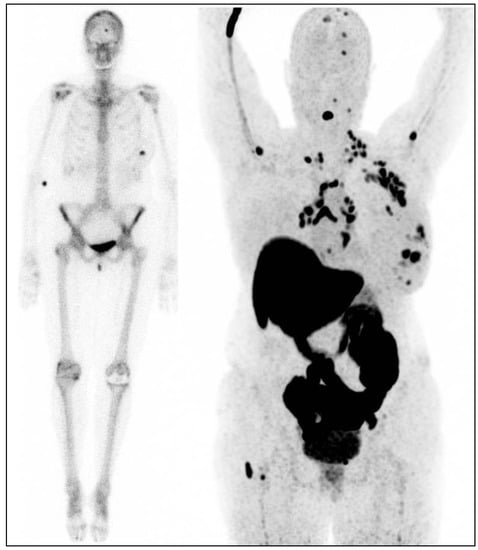

- Venema, C.M.; Mammatas, L.H.; Schroder, C.P.; van Kruchten, M.; Apollonio, G.; Glaudemans, A.W.J.M.; Bongaerts, A.H.H.; Hoekstra, O.S.; Verheul, H.M.W.; Boven, E.; et al. Androgen and estrogen receptor imaging in metastatic breast cancer patients as a surrogate for tissue biopsies. J. Nucl. Med. 2017, 58, 1906–1912. [Google Scholar] [CrossRef]